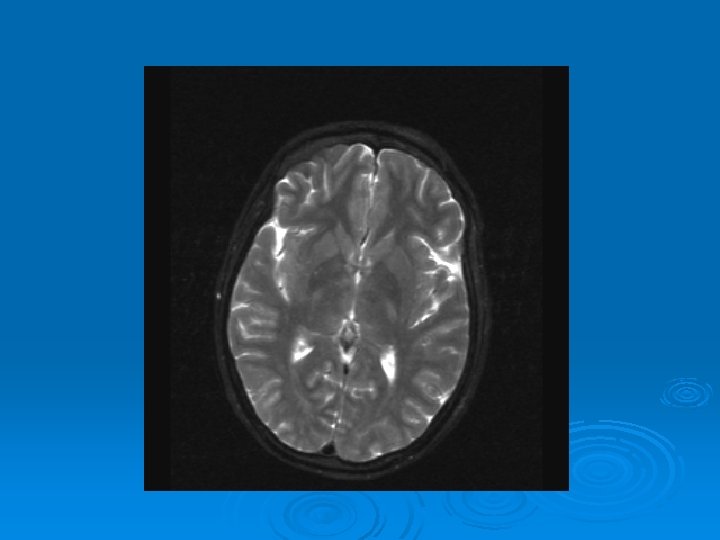

MRI: 2/9/2007 Ø 1. Leptomeningeal enhancement, most prominently seen over the posterior parietal and occipital lobes.

CMV: Ventriculoencephalitis Ø Clinical: Can have abrupt presentation of confusion, apathy, impaired memory, withdrawal, nystagmus, motor weakness, cranial nerve deficits, ataxia, seizures, coma. Can rapidly progress. Ø Labs: CSF: Monocytic Pleocytosis, Low Glucose CMV PCR Positive in CSF: (Sensitivity, Specifity 80, 90%, PPV, NPV, 86 -92, 9598%) Serum CMV viremia Ø Ø Ø MRI: Subependymal enhancement, diffuse hyperintense T 2 WI, ventriculomegaly.

MRI of CMV patient Magnetic resonance images of a patient with cytomegalovirus ventriculitis Ependymal enhancement after injection of gadolinium. DPTA seen on coronal T 1 -weighted image. Ø Highly abnormal ependmal signal on proton densityweighted image of the brain in axial section. Ø Ø See images in: l Arribas et al, Cytomegalovirus Encephalitis, Annals of Internal Medicine, 1996, Vol 125, Issue 7